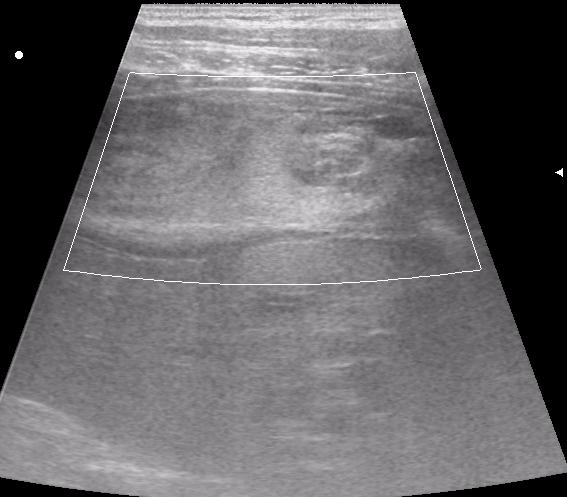

сегодня был селезёночный день.

мальчик лежал на спине (переломы костей таза). на затёки крови не похоже.